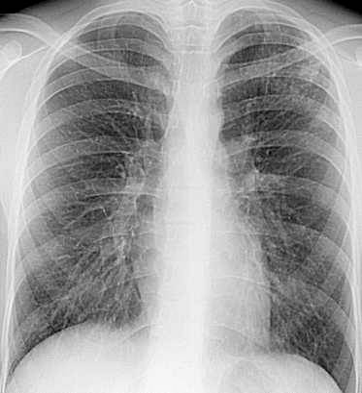

Рис. 1. Больной Ш., 19

лет. Обзорная рентгенограмма.

Очаговый туберкулез. Справа в подключичной зоне на фоне фиброзных изменений

определяются множественные очаги средней плотности